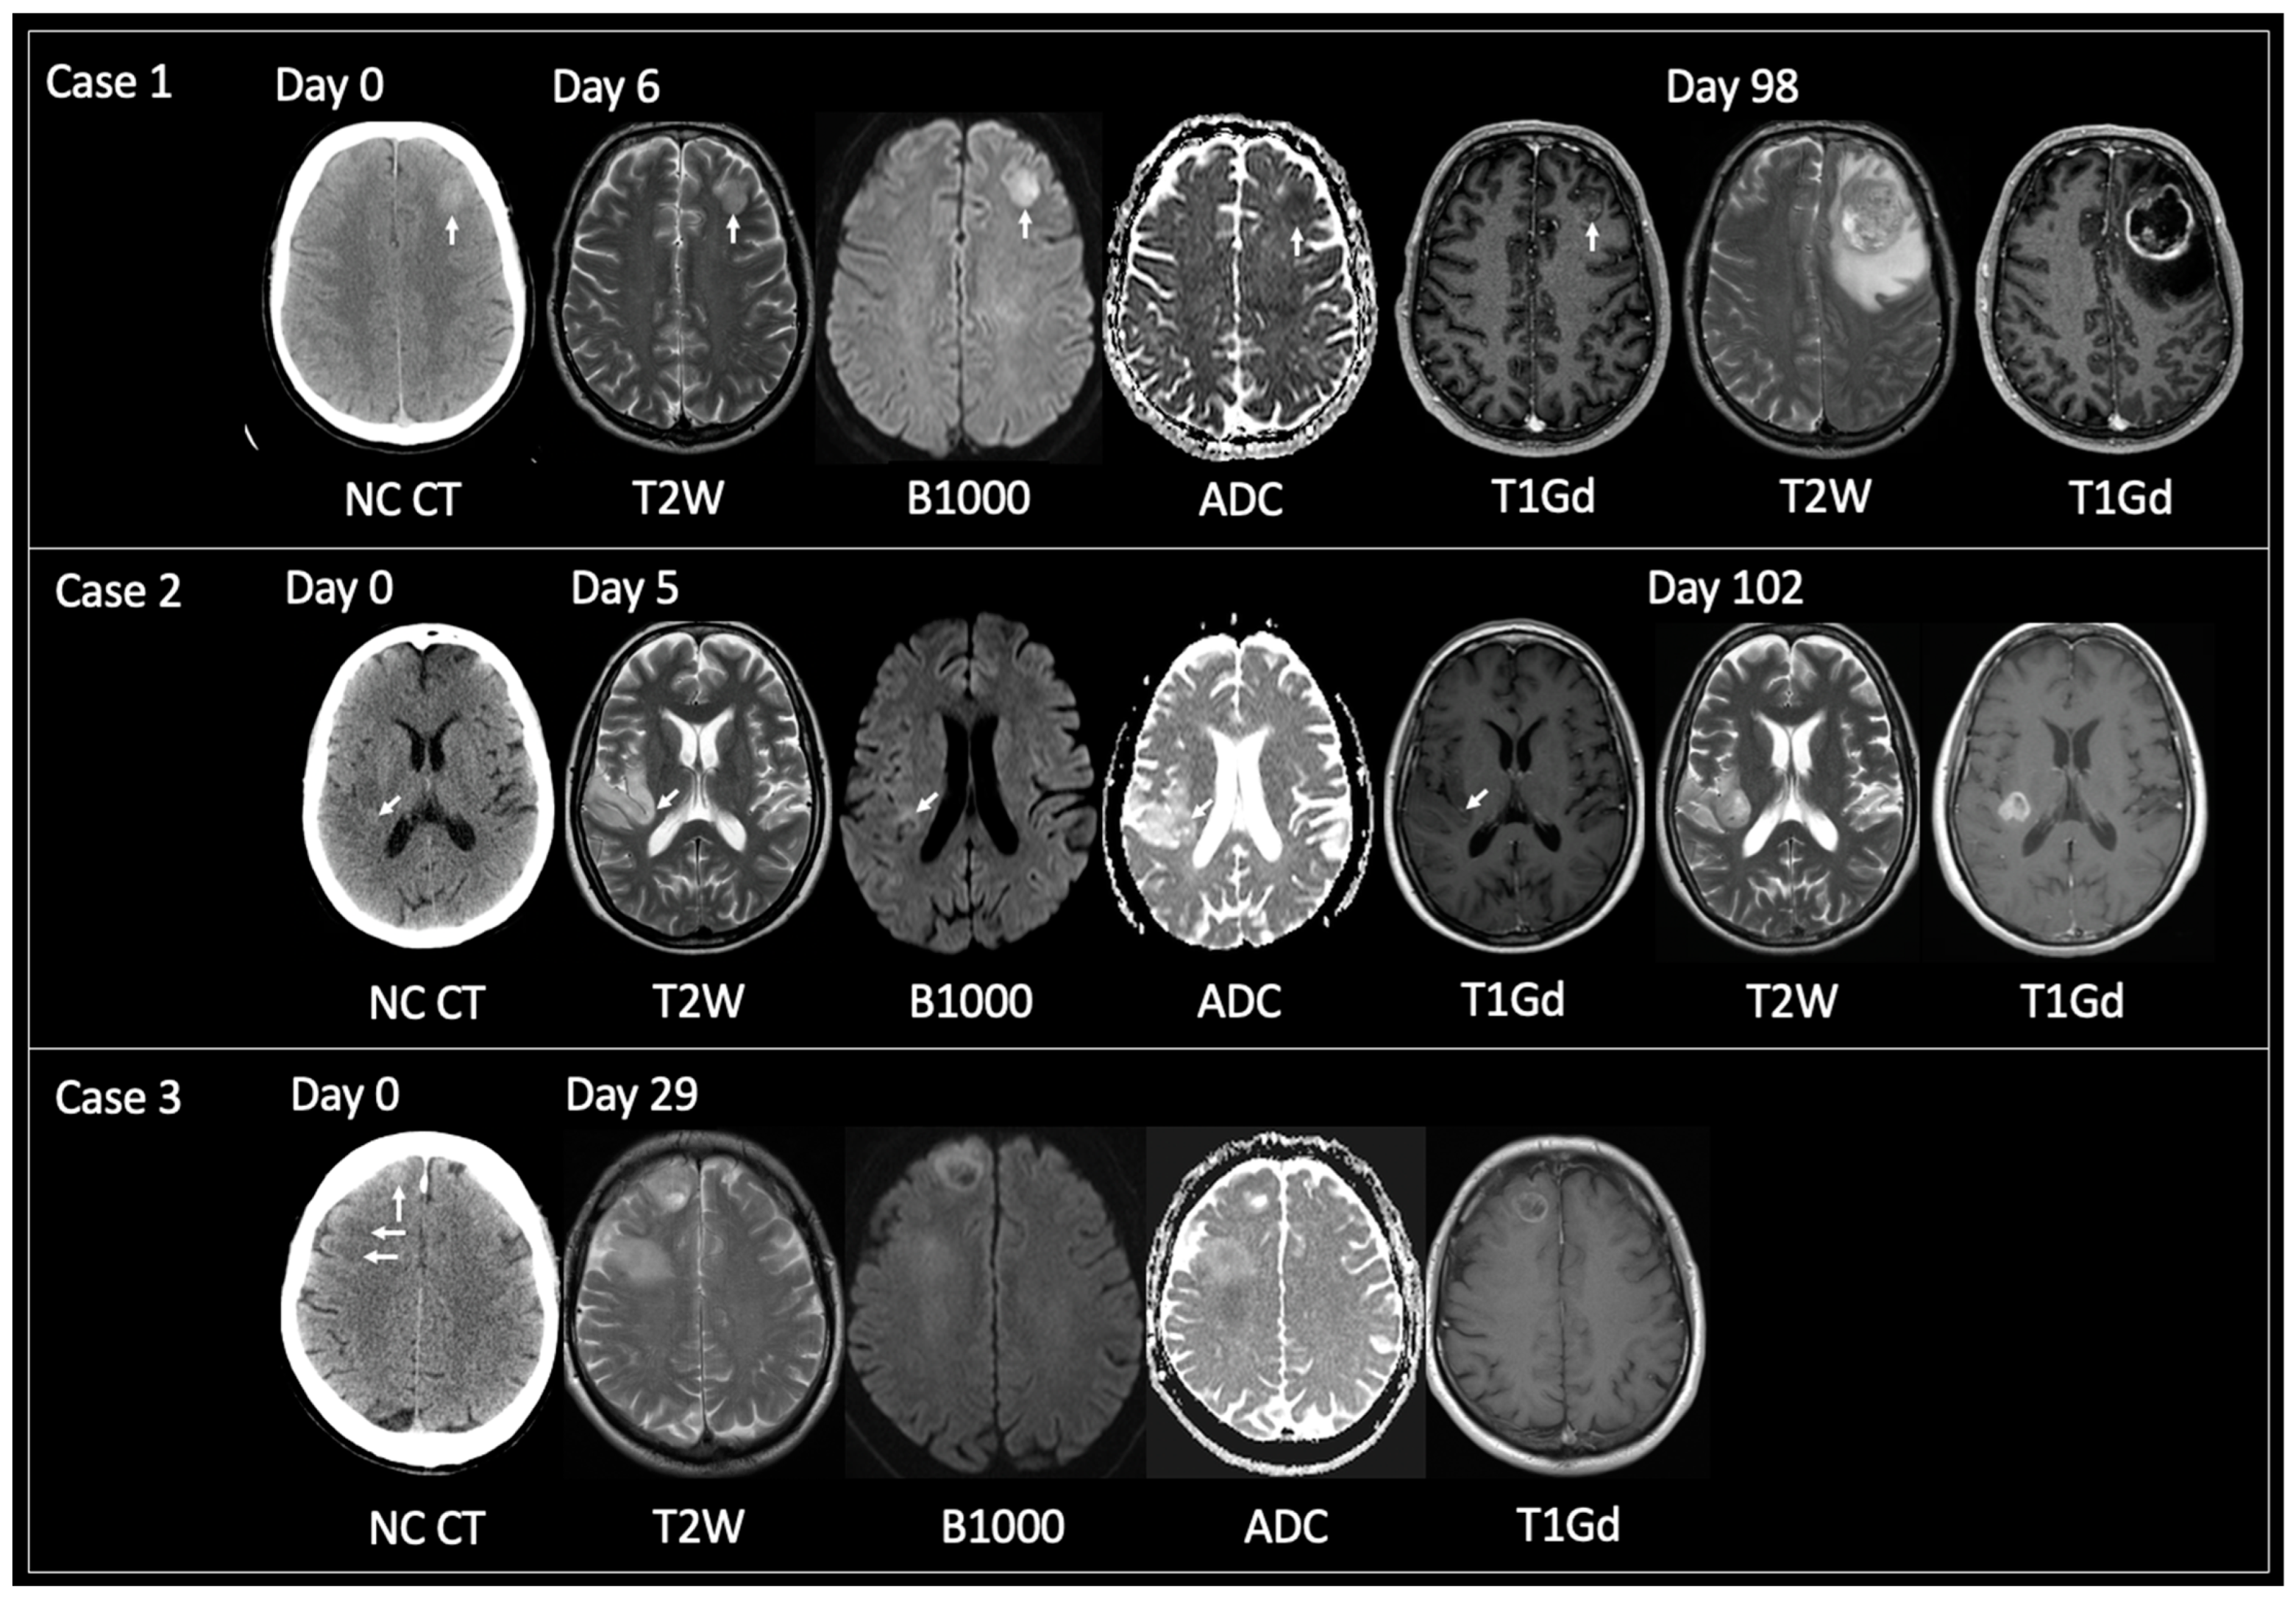

Mean time from CT hyperdensity to TRA GBM (n = 38) = 74 days (range 7–158); solitary lesions only (n = 32) = 69 days (7–158); >1 locus only (n = 6) = 95 days (46–147). Figure 3 displays examples of solitary lesions with TRA GBM at the time of tissue sampling with preceding imaging. Note cases 2 and 3 that show intratumoral foci of CT hyperdensity that progress at a faster rate than the rest of the tumor.

Figure 3.

Examples of solitary lesions with TRA GBM at tissue diagnosis that had preceding imaging. Case 1: 56-year-old male presented with seizures. Unenhanced CT on day 0 showed a hyperdense lesion in the left frontal lobe. This had corresponding T2 iso signal with reduced diffusivity and central nodular enhancement on MRI day 6. TRA GBM followed on MRI day 98. Case 2: 53-year-old female presented with several days of intermittent left-sided anesthesia. Initial unenhanced CT day 0 showed a focus of hyperdensity within the posterior aspect of the right insula (arrow) with adjacent cortical low density. MRI day 5 revealed an infiltrative glioma within the right inferior parietal lobule and right insular with the focus of prior CT hyperdensity corresponding to T2 iso signal, reduced diffusivity and containing a tiny dot of enhancement (arrows). MRI day 102 showed TRA GBM at the site of the prior CT hyperdense focus but relative stability of the rest of the non-enhancing tumor. Case 3: 63-year-old male presented with seizures. Unenhanced CT day 0 revealed two abnormal areas: a hyperdense focus anteriorly in the right superior frontal gyrus (vertical arrow) and subcortical hypodensity in the right middle frontal gyrus (horizontal arrows). These foci were linked by hypodensity (not shown) correlating with one diffuse tumor. MRI day 29 demonstrated interval growth of the previously hyperdense lesion, showing TRA GBM with enhancing periphery and central necrosis. Note how the peripheral tumoral tissue shows T2 iso solid signal with reduced diffusivity and enhancement. MRI day 29 also showed progression of the previously low-density lesion but not to TRA GBM. This lesion was shown to infiltrate into the deep white matter of the right centrum semiovale, contain areas of reduced diffusivity but no enhancement. TRA GBM—typical radiological appearance of glioblastoma, NC CT—non-contrast CT, T2W—T2-weighted, B1000—DWI, ADC—apparent diffusion coefficient map of DWI, T1Gd—T1-weighted post-gadolinium.